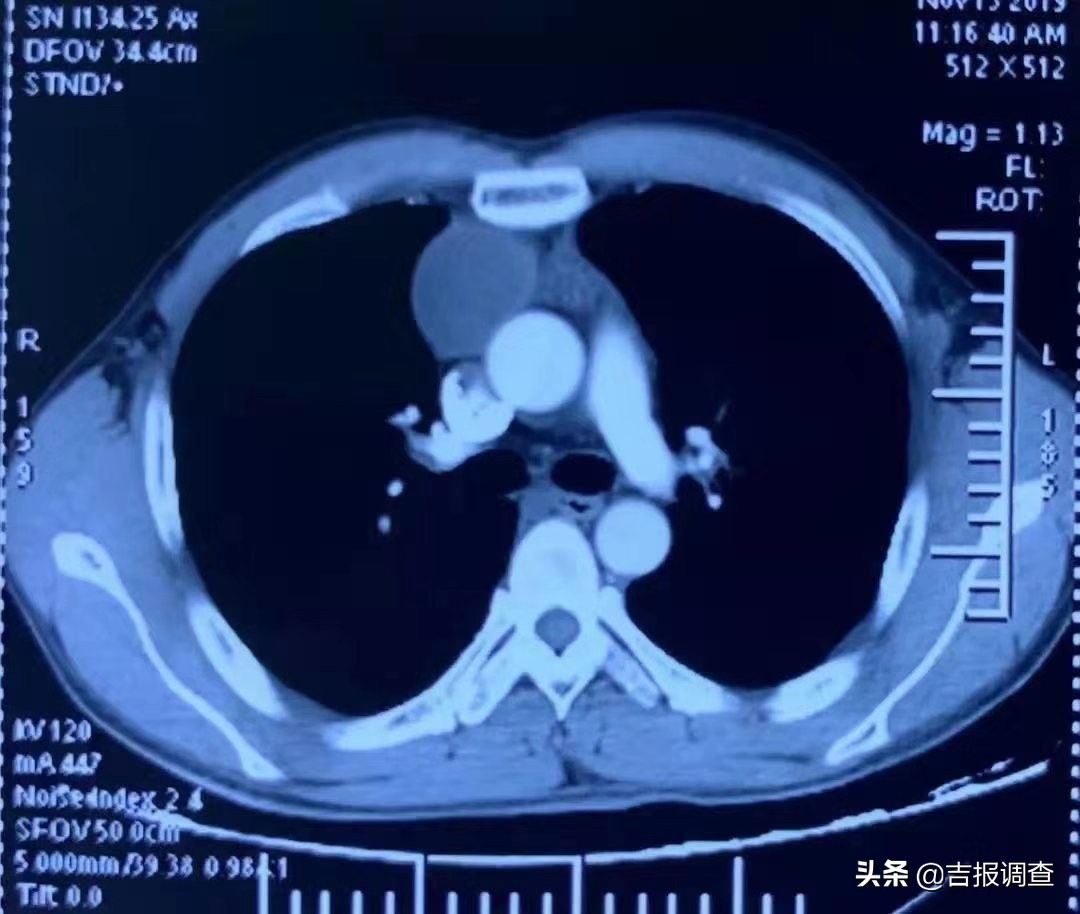

今年35岁的高仁助(化名),是吉林国文医院职工,在体检时发现患有剑突下入路纵隔肿瘤:前纵隔4cm占位,且伴有胸腺增生,因为工作的原因,他知道北京大学肿瘤医院胸外科杨跃主任在胸部肿瘤外科治疗方面造诣颇深,也知道杨跃每周都会在医院会诊、手术,于是立即与吉林国文医院胸外科医生取得联系。

体检发现前纵隔肿瘤及胸腺增生